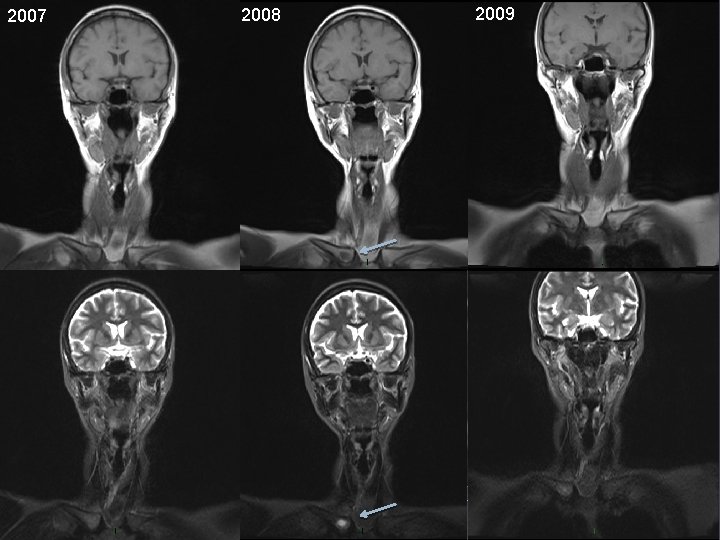

2008 2007 24 2009

Critères de réponse tumorale Bilan initial ADC Après traitement Myélom e 25 ADC = 0, 891. 10 -3 cm 2/sec Diff b=1000